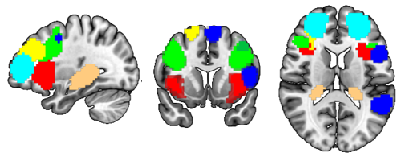

To identify the top ROIs for the intelligence prediction tasks, we first extracted the pooled ROIs after passing through the first layer of TopK Pool layer of a fully trained model using a holdout test set. We then selected the ROIs with highest frequency across each of the samples for all the intelligence scores. For fluid intelligence, we selected two ROIs (Middle Temporal Gyrus, and Middle Frontal Gyrus) (Fig 2(a)) with 90% frequency threshold. Similarly, for crystallized intelligence, middle frontal gyrus and caudate were selected with a frequency threshold of 90% (Fig 2(b)). For total composite scores, as the pooling ratio from hyper-parameter tuning was higher (0.78), we were able to extract 21 brain regions for 95% frequency. We categorized the selected regions into seven connectivity networks and plotted them independently in Fig. 3.

Refer to caption

(a) Cognitive Control Network

(b) Default Mode Network

(c) Sensorimotor Network

(d) Subcortical Network

(e) Visual Network

(f) Cerebellar Networks

Figure 3: Significant regions expressed as Connectivity Networks for Total Composite Scores

The diverse set of brain regions identified as relevant for total composite score reflects the intricate and distributed nature of cognitive processes, as well as the general and broad attribute of ’intelligence’. These regions cover six relatively separate brain networks. Sensorimotor network (postcentral gyrus) and visual network(middle/inferior occipital gyri, calcarine cortex, cuneus, fusiform) involve basic functions of various sensory inputs (J;Tadi ) and further integration of inputs (BrainMadeSimple (2022)). The cognitive control network covers particularly frontal-parietal regions (superior/middle frontal gyri, supplementary motor area, insula, hippocampal) and participates in various higher-order cognitive processes (Jacques et al. (2018)), such as executive function, attention, working memory, and planning (Tanji and Shima (1994)). The default network comprises the anterior cingulate cortex, posterior cingulate cortex, and precuneus and reflects the brain’s intrinsic activity in contrast to task-oriented controls (Zanto and Gazzaley (2013)). Their functions are linked to self-referential thinking (Raichle (2015)), introspection, and episodic memory retrieval (Gusnard et al. (2001)). Subcortical network, precisely caudate as discussed before has a role in learning and memory and has been shown to be able to predict IQ (Vincent et al. (2006)). Last but not the least is the cerebellum. Its function is well recognized to be beyond motor function, but subserving cognition (Koziol et al. (2011)), and recently cerebellum has been partitioned to echo the 7 cortical networks (King et al. (2019)). In summary, the interplay of these diverse brain regions likely contributes to the complexity of cognitive processes that manifest as Total Composite Scores. The extensive network of regions suggests that intelligence is not confined to a single brain area but rather emerges from the collaboration of numerous interconnected regions, each contributing its unique specialization to overall cognitive performance.